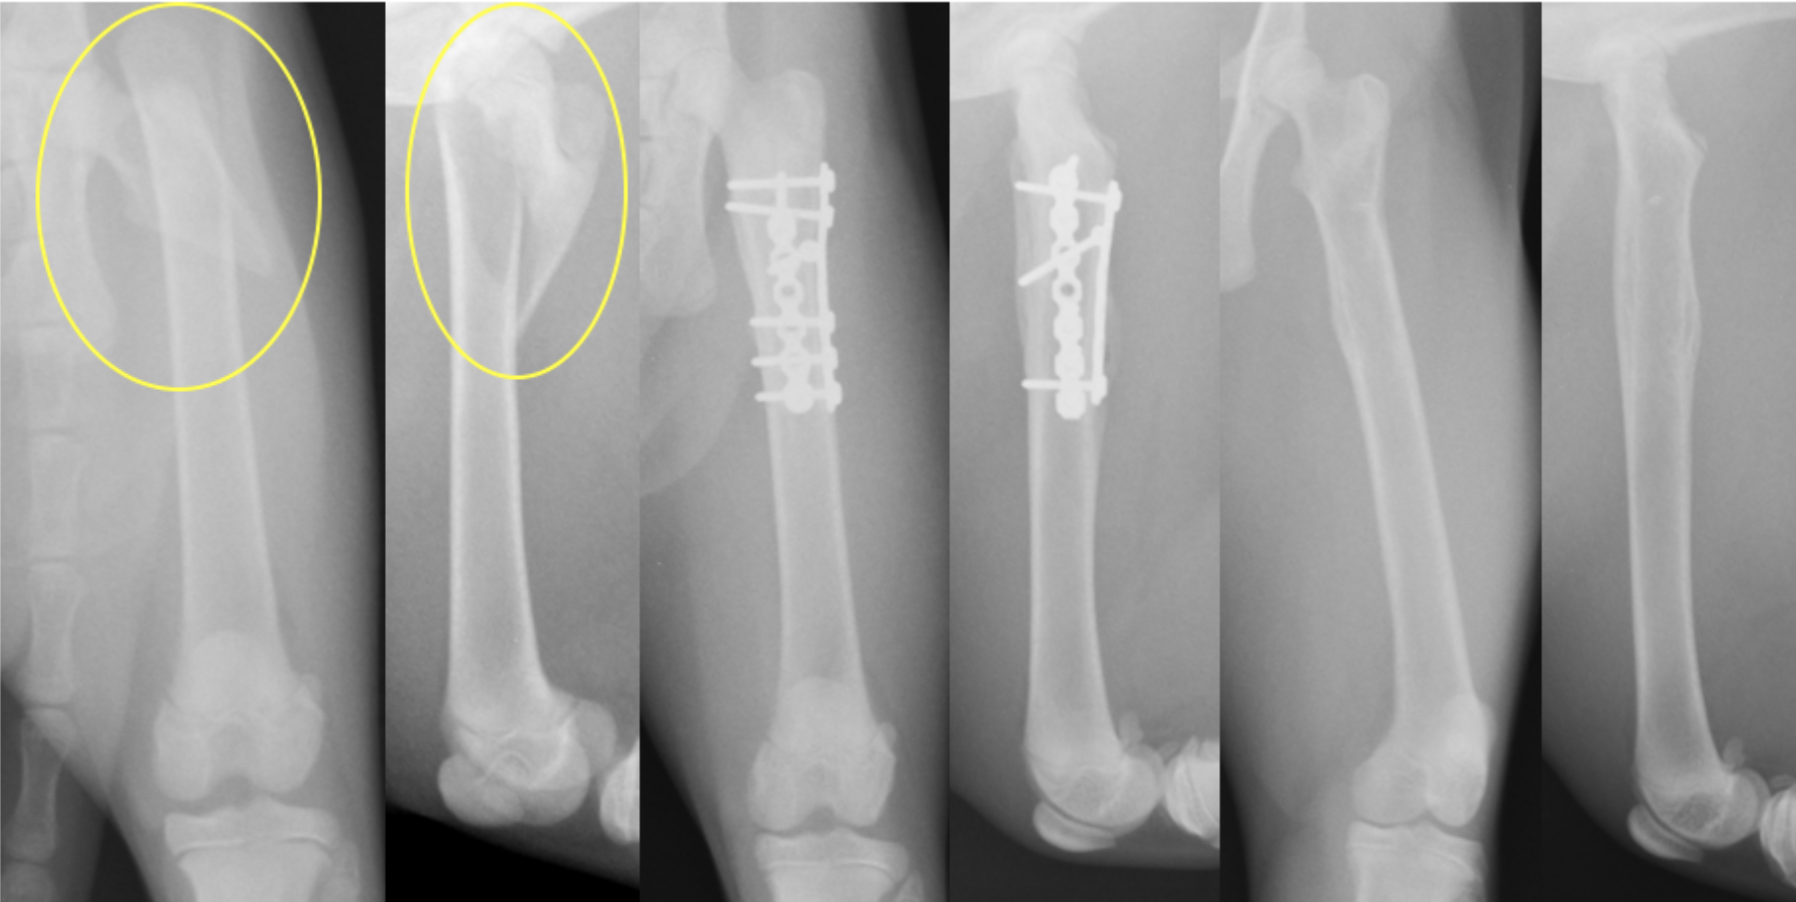

老齢猫の大腿骨骨幹部中央の斜骨折です。老齢猫では骨が固く、もろくなっていくので簡単に骨が割れていくことがあります。

なるべくそうならないよう髄内ピンを設置してからプレート設置を行いましたが、それでも数箇所割れてしまったところがあります。SOPプレートというロッキングプレートの一種で固定しています。老齢のため、骨化を促進するためフリーズドライのパウダーを入れています(写真右)

術後レントゲンです。アライメント(向きや配置)も問題なく固定されています。術後すぐに歩きだし、3週後には走り回って、家を脱走するくらいとのことでした。